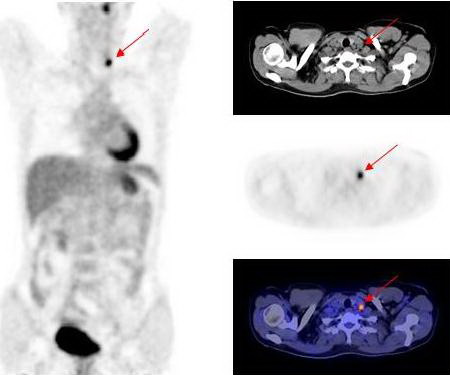

Hình 4: Hình ảnh di căn hạch thượng đòn trái

Kết quả PET/CT: tổn thương tăng hấp thu FDG mạnh tại vòm họng bên trái, max SUV=11,8, các tổn thương di căn hạch tại vùng cổ bên phải và bên trái.

Trong khi đó kết quả nội soi vòm họng và CT không phát hiện thấy tổn thương u nguyên phát (CT-) bởi vì tổn thương ở mức độ chưa xâm lấn ra bề mặt niêm mạc vòm họng và mà mắt chưa thể nhận thấy được  qua  nội soi, CT...

Dựa vào các kết quả trên, bệnh nhân được chẩn đoán là ung thư vòm họng di căn hạch cổ hai bên. Đồng thời đánh giá được giai đoạn bệnh của bệnh nhân là T1N2M0, kế hoạch điều trị tiếp theo là xạ trị phối hợp hoá trị.